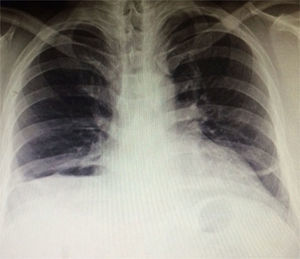

Caso clínicoSe presenta el caso de un paciente masculino de 34 años de edad sin antecedentes médicos de importancia. Su enfermedad comienza hace 3 años con mareos, diaforesis, disnea leve intermitente y recientemente arritmia cardíaca. En examen físico presenta hipoventilación y matidez en base pulmonar derecha, así como dolor leve al comprimir el epigastrio. Se realizan exámenes complementarios con: a) radiografía de tórax compatible con hernia diafragmática derecha (fig. 1); b) trago con contraste hidrosoluble (fig. 2) con ascenso al tórax de colon y estómago con rotación mesentérico axial, y c) TAC (figs. 3 y 4) que confirma HM (fig. 5).

Se lleva a cabo abordaje laparoscópico con defecto de 10×10cm y contenido herniario de epiplón, estómago, colon y lóbulo izquierdo del hígado. Se reduce sin complicaciones y se repara con malla de doble capa fija con tackers. La radiografía de control resulta satisfactoria y el paciente egresa sin complicaciones el 2.o día postoperatorio.